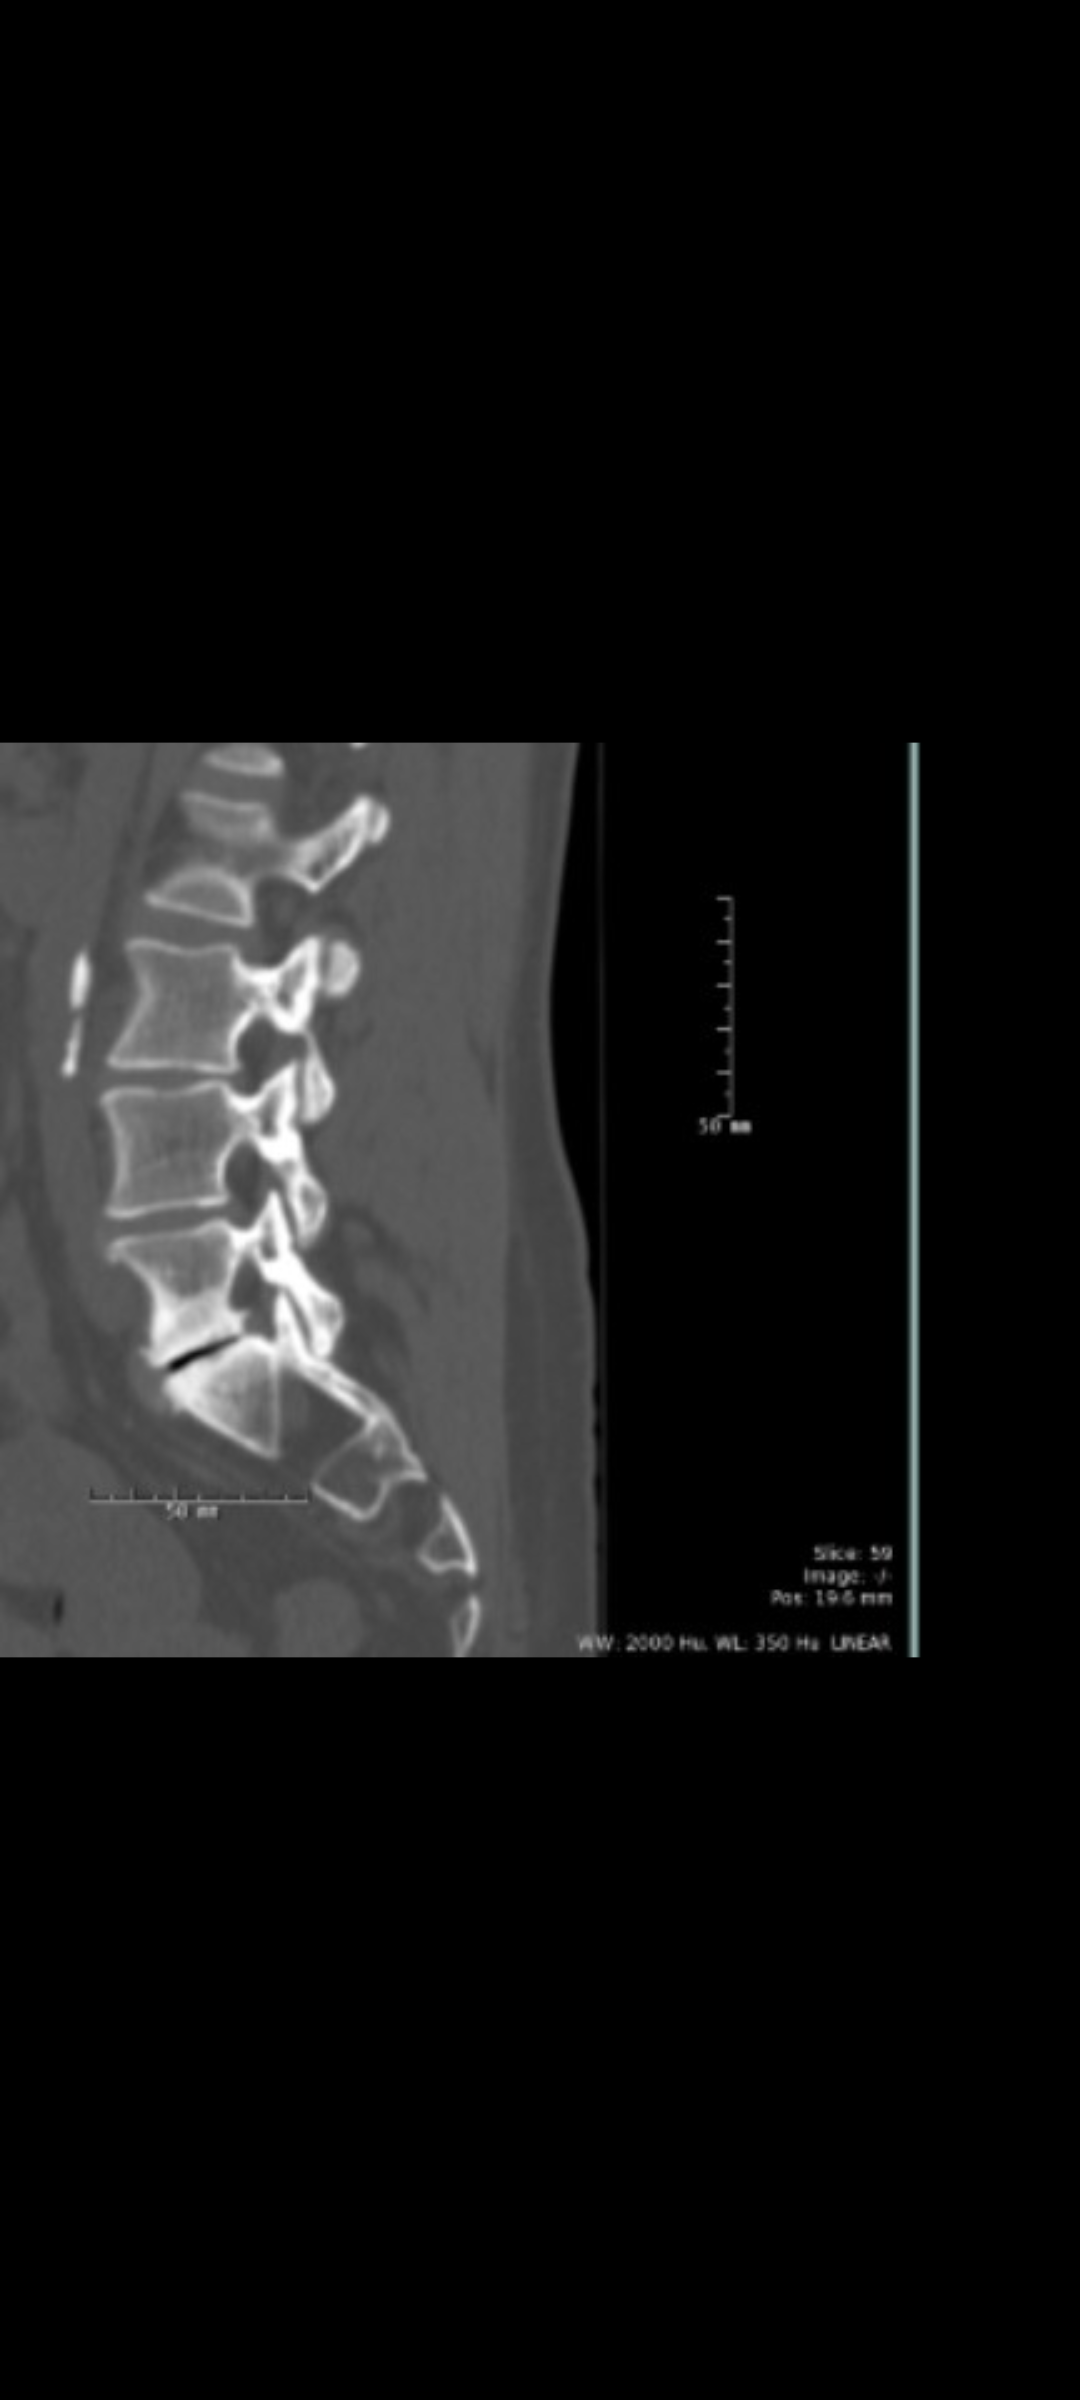

I’ve been diagnosed with degenerative disc disease and spinal stenosis, which have caused years of chronic pain and nerve compression.

Those falls accelerated everything. What was once “eventually” became “as soon as possible.” Since then, I’ve been undergoing a nerve ablation series in my cervical spine to help manage the upper spine and neck pain while preparing for the lumbar spinal fusion (L4–S1) scheduled for December 18, 2025, at Rush University Medical Center.